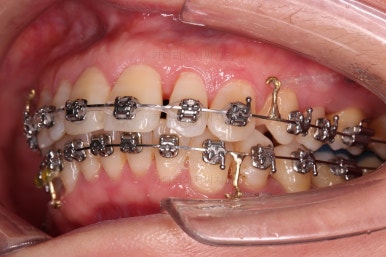

비발치 치료에서 핵심되는 장치가 미니스크류에요.

위 사진에서도 어금니쪽 잇몸 부위를 보시면 아주 작은 금속성 나사머리가 보이실건데요. 나사로 단단히 지탱해주고 치열을 뒤로 당겨주는 원리죠.

중간중간 얼굴모습도 확인을 해주고요.

치료의 막바지인데도 불구하고 아직 앞니쪽에 틈이 보이죠?

틈새는 가장 마지막에 모이게 될거에요.

디테일을 조절하고 교합을 더 맞추고 원하시는만큼 입을 더 넣고 부산성인교정 마무리를 하기로 했어요.